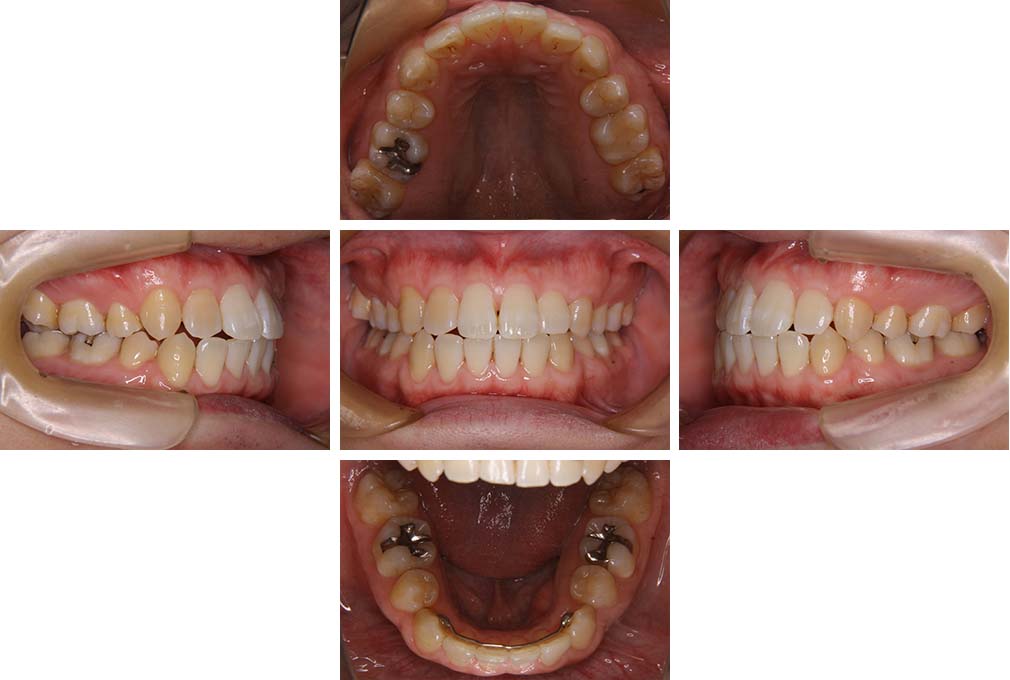

CASE:02

下顎前歯部叢生、小臼歯4歯先天欠損

初診時年齢 14歳3か月

性別 女性

治療費の目安 70万円(治療開始時)

上顎左右側小臼歯3歯、下顎左側第二小臼歯の先天欠損と下顎前歯の叢生を主訴として近隣一般歯科から紹介来院した。

上顎左側第一、第二小臼歯、右側第一小臼歯、下顎左側第二小臼歯が先天欠損であったが、左上第二乳臼歯の根の吸収がほぼ無いことから、これを残すこととして、下顎左側乳臼歯と、右側第二小臼歯を抜歯していただきマルチブラケット装置を使用して動的治療を行った。矯正用ゴムなどの協力状態も良く2年0カ月(調整来院19回)で装置を撤去し保定へ移行した。動的治療終了13年2カ月での来院時には下顎左右側智歯が萌出していたが、垂直的に萌出していたため抜歯は行っていない。

治療前

14歳3か月

治療後

動的治療期間2年0カ月

16歳7か月

13年経過

動的治療終了後13年2カ月

30歳0か月